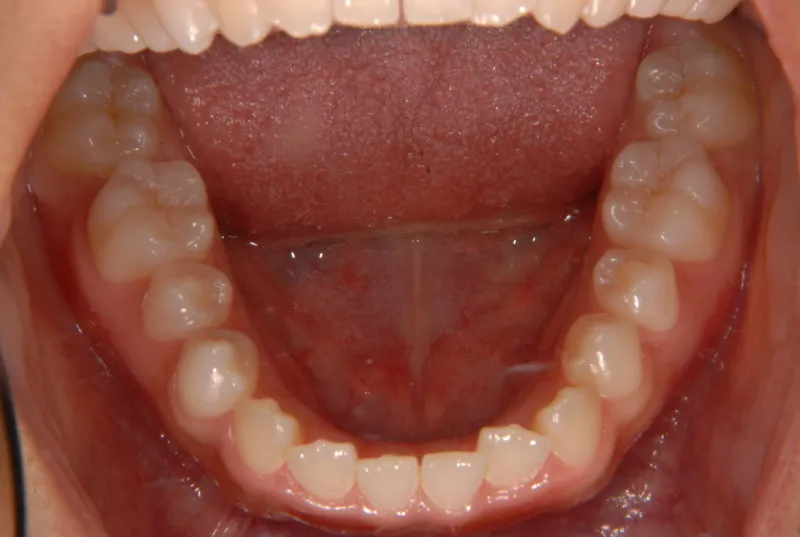

開咬・舌癖・18歳女性

初診時年齢 高校生 (女性) 主訴 開咬 舌癖

状態 前歯で噛めない(開咬/オープンバイト)